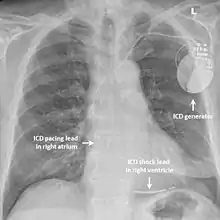

Implantable cardioverter-defibrillator

While medication and sympathectomy aim to prevent abnormal heart rhythms from occurring in the first place, an implantable defibrillator (ICD) may be used to treat arrhythmias that medication has failed to prevent and restore a normal heart rhythm.[2] These devices, usually implanted under the skin at the front of the chest below the shoulder, can continuously monitor the heart for abnormal heart rhythms. If a life-threatening arrhythmia is detected, the device can deliver a small electric shock to terminate the abnormal rhythm and restart the heart.[1]

Implantable defibrillators are often recommended for those with CPVT who have experienced blackouts, ventricular arrhythmias or cardiac arrest despite taking appropriate medication.[2] These devices are life-saving, as it has been shown that their use confers a significant survival benefit in patients with CPVT.[25] It has been suggested that the resulting surge of adrenaline caused by the pain of an electric shock from the device could theoretically bring on a cycle of recurrent arrhythmias and shocks known as an electrical storm,[4] and therefore it is strongly recommended that those with an ICD implanted for CPVT take a beta blocker to dampen the effects of adrenaline.[4]